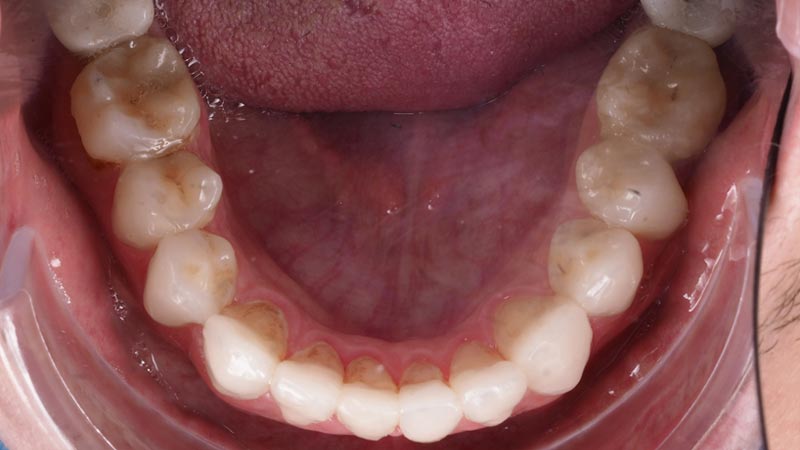

“Paciente joven que acude a la clínica con caries y desgastes generalizados en toda la boca.”

En una primera visita realizamos un estudio estético para valorar y aumento de dimensión vertical para mejorar su sonrisa y oclusión.

Tras valorar el estudio realizamos una rehabilitación completa mediante carillas de cerámica para solucionar su problema de desgastes y caries radiculares que presentaba y mejorar el aspecto de su sonrisa.